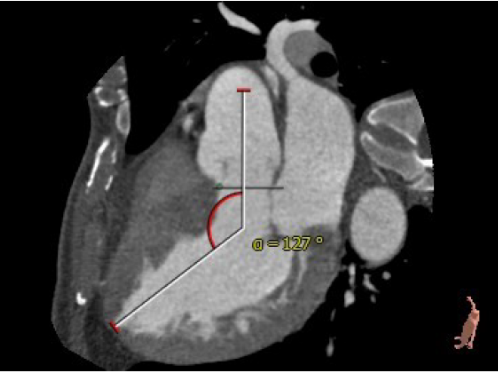

主动脉与左心室夹角:127°

主动脉瓣环平面水平夹角:60°

本例患者为横位心重度主动脉瓣反流,升主动脉近端增宽,其特殊的解剖结构会增加手术难度,甚至可能影响手术成功率。如采取传统常规的经股入路,经导管介入瓣膜很难保持与主动脉瓣环平面垂直的同轴性,跨瓣环平面的难度大。经心尖途径的J-Valve系统距离短,操作方便,对于横位心的患者依然可以较好的保持瓣膜支架的同轴性。同时其短支架设计,以及形似 “皇冠”的支架顶部设计为冠脉口留有充足空间,起到很好的冠脉保护作用。